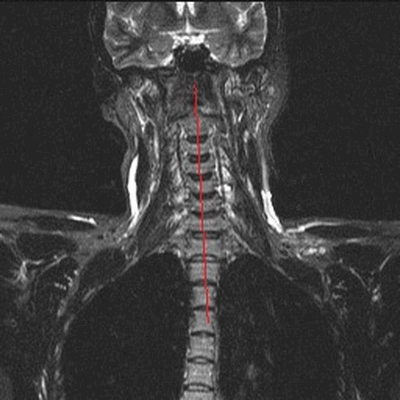

МРТ шеи: оценка сколиоза (коронарная плоскость, Т2 последовательность, STIR)

Боль в шее может быть вызвана проблемой в самом позвоночнике или в окружающих его мышцах. Наиболее часто дискомфорт в данной анатомической области обусловлен остеохондрозом, грыжей или протрузией межпозвонковых дисков, компрессией нервно-сосудистых пучков, иннервирующих спинной мозг, невралгией. Перед тем, как сделать выбор в пользу МРТ, врач оценивает характер боли и ее локализацию. Неприятные ощущения в области передней части шеи чаще свидетельствуют о заболевании трахеи, гортани, щитовидной железы, воспаленных лимфатических узлах, осложнениях со стороны уха. Для постановки диагноза в описанных ситуациях иногда достаточно проведения физикального и инструментального осмотра, ультразвуковой сонографии. Если пациент предъявляет жалобы на боль в задней поверхности шеи, усиливающуюся при повороте или наклоне головы, прострелы, ограничение в подвижности - для обнаружения проблемы обосновано сделать МРТ шейного отдела позвоночника. Магнитно-резонансное сканирование показывает структурные изменения в области интереса. Если боль носит функциональный характер, например, сопутствует миозиту, лучевая диагностика будет малоинформативна.

Показания и противопоказания к томографии шейного отдела

МРТ шеи: перелом зубовидного отростка, миелопатия (дисфункция спинного мозга в области поврежденных шейных позвонков) в коронарной плоскости (Т2 последовательность, STIR)